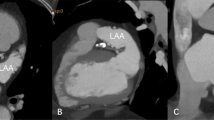

Cardiac CT is an accurate, noninvasive imaging modality for the detection of LAA thrombi, particularly when delayed imaging acquisition protocols are used

Kim, S. C. et al. Differentiation between spontaneous echocardiographic contrast and left atrial appendage thrombus in patients with suspected embolic stroke using two-phase multidetector computed tomography. Am. J. Cardiol. 106, 1174–1181 (2010).

Hur, J. et al. Dual-enhancement cardiac computed tomography for assessing left atrial thrombus and pulmonary veins before radiofrequency catheter ablation for atrial fibrillation. Am. J. Cardiol. 112, 238–244 (2013).

Hur, J. et al. Thrombus in the left atrial appendage in stroke patients: detection with cardiac CT angiography—a preliminary report. Radiology 249, 81–87 (2008).

Hur, J. et al. Left atrial appendage thrombi in stroke patients: detection with two-phase cardiac CT angiography versus transesophageal echocardiography. Radiology 251, 683–690 (2009).

Hur, J. et al. Cardioembolic stroke: dual-energy cardiac CT for differentiation of left atrial appendage thrombus and circulatory stasis. Radiology 263, 688–695 (2012).

Hur, J. et al. Dual-enhanced cardiac CT for detection of left atrial appendage thrombus in patients with stroke: a prospective comparison study with transesophageal echocardiography. Stroke 42, 2471–2477 (2011).

Romero, J. et al. Detection of left atrial appendage thrombus by cardiac computed tomography in patients with atrial fibrillation: a meta-analysis. Circ. Cardiovasc. Imaging 6, 185–194 (2013).